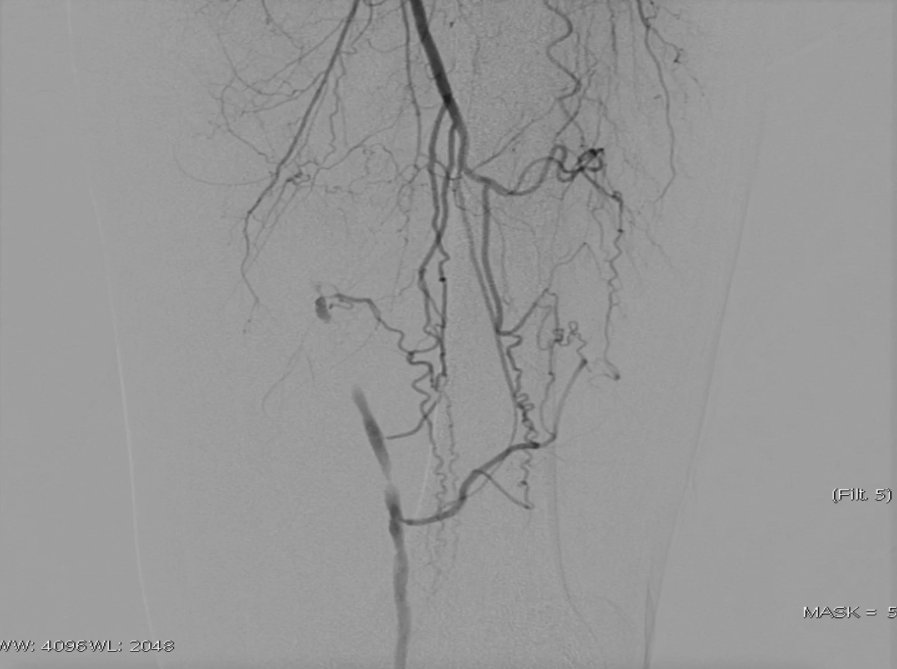

穿刺右侧股总动脉,置入8F翻山鞘,行左下肢动脉造影,可见左股浅动脉长段闭塞,远端流出道尚通畅。

既往支架已遮盖股浅动脉起始段